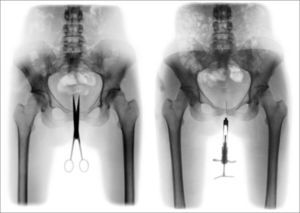

Si todo cuerpo muerto es lo vivo reducido a su imagen, su contrapartida es que toda imagen es vida muerta en busca de un cuerpo. Y desde las entrañas indiferenciadas de la nueva imagen, el deseo de cuerpo que las habita encuentra su expresión más punzante. Expresión que no es ya, como señalaba Hannah Arendt, la de la interioridad “de una idea, de un pensamiento, de una emoción”, sino “expresividad de una apariencia”, que no expresa nada a no ser a sí misma (30). En los Retratos íntimos de Cris Bierrenbach (figs. 7 y 8), el dolor se vuelve un imperativo de la propia imagen. En tanto que en la “fotografía vaciada” de Dabdab, la sustancia inmaterial de lo digital disuelve las distinciones que solo las palabras de la leyenda insisten en preservar; en estos retratos, materia e imagen están en tensión permanente. Tensión de la que ahora ninguna palabra puede dar cuenta.

La tijera y la jeringa no cesan de convocar a la carne de la imagen y, simultáneamente, frustrar su encarnación. Ya no es necesario decir, como el Dr. Röntgen, que se trata de la “mano viva” de su esposa, cuya devoción un anillo testimonia. Huesos vivos ya nos son familiares y el metal ya no los envuelve, como un pequeño círculo protector: el metal instiga, perfora. De esta nueva condición de las relaciones de las imágenes entre sí (y de la fotografía con el mundo), Roberta Dabdab hizo anamnesis y Cris Bierrenbach el reporte de autopsia: agotada de tanto decir, vaciada de su magia, la fotografía despojada de palabras reencuentra en el grito lacerante el único modo de dar voz a lo real que subsiste en las entrañas de la realidad. Por intermedio de este grito, el cuerpo retorna como la Tierra prometida de las imágenes.